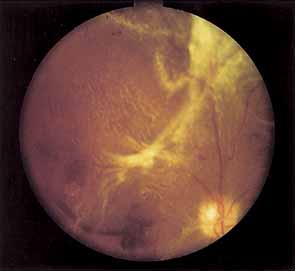

Proliferative vessels usually arise from veins and often begin as a collection of fine vessels. When they arise on or within 1 disc diameter of the optic disc they are referred to as neovascularization of the disc (NVD) (Fig. 9). When they arise further than 1 disc diameter away, they are called neovascularization elsewhere (NVE) (Fig. 10). NVE nearly always grows toward and into zones of retinal capillary nonperfusion, but capillary nonperfusion is nearly always more widespread in eyes with NVD than it is in NVE.12 Interestingly, it is seen more often in patients younger than 40 compared to older patients with diabetes.13

Fig. 9 Advanced neovascularization of the disc.